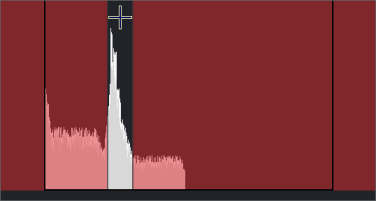

Az Ablakolás eszköztár bal oldali végén lévő mezőértékektől jobbra lévő kis nyíl egy lenyíló menü. Hisztogram megjelenítéséhez válassza ki a jobb oldali  lefelé mutató nyilat.

lefelé mutató nyilat.

Kattintson és tartsa lenyomva a + jelet a hisztogram közepe közelében, és húzza különböző irányokba a W és L számok módosításához. A kép ennek megfelelően módosul.